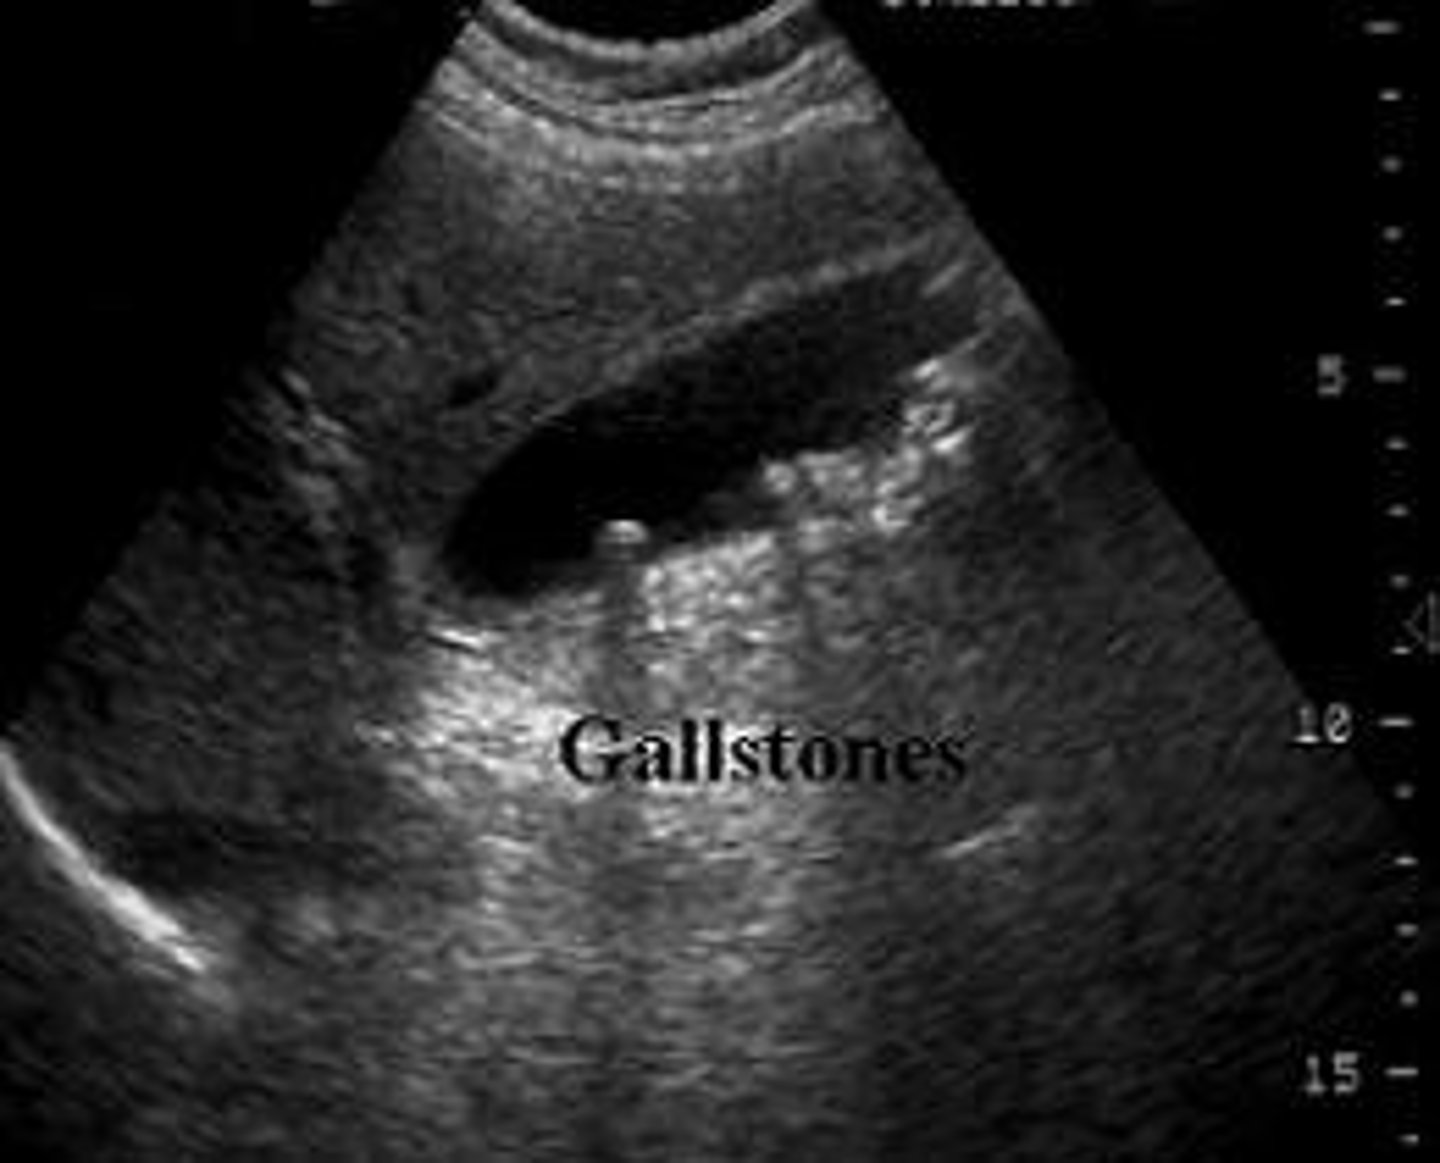

Cholelithiasis

*****MOST COMMON DISEASE OF GB*****

- biliary stones found in the GB are called gallstones

Cholelithiasis sonographic findings

- mobile, echogenic structure within GB lumen that produces posterior shadowing

-WES sign if completely filled with stones

-change in patient position that shows movement